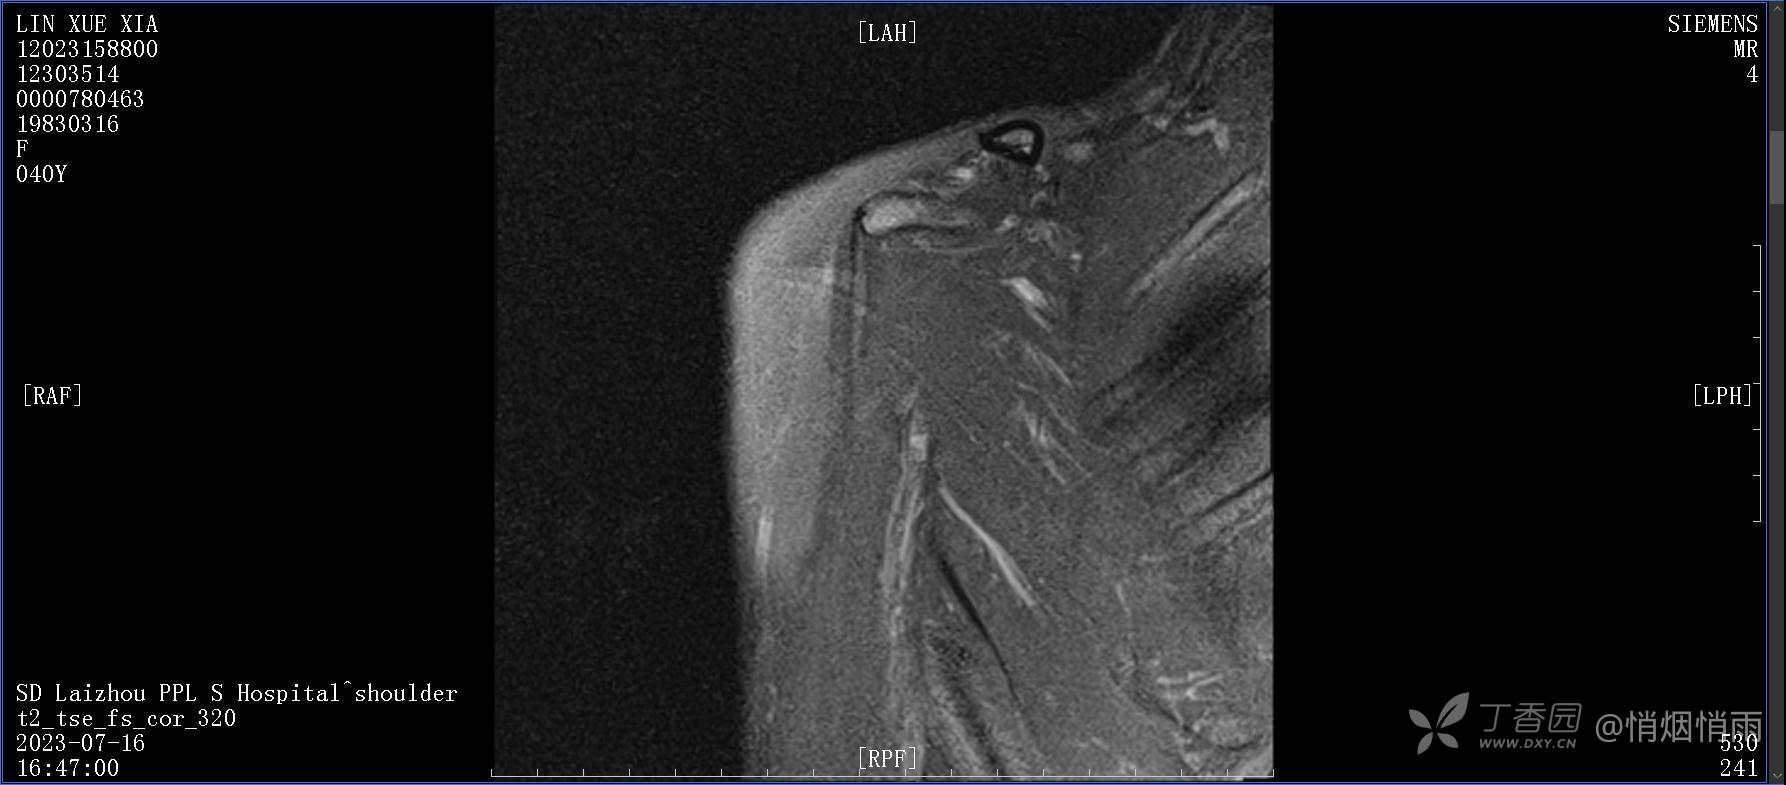

查体:右肩关节局部轻度肿胀,肩胛区压痛明显,痛处不固定,肩关节痛性活动受限,jobe test(+),lift -off test(+),中指、环指感觉较余指减退,余肢端感觉及血运情况可。

目前的诊断,暂时依据辅助检查诊为肩袖损伤,但是患者疼痛的性质和特点,却不是单纯的肩袖损伤所致。考虑过胸廓出口综合征,但是该疾病会出现肩胛区的疼痛吗?(由于考虑到费用的问题,没再进行下一步的检查)带状疱疹会有如此的症状吗?